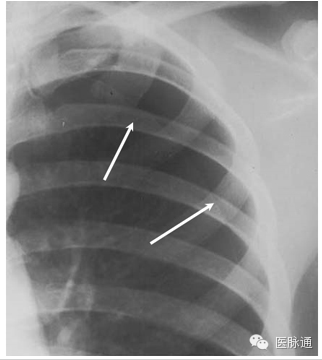

当空气进入到脏层和壁层之间的胸膜腔可发生气胸。原发性自发性气胸的发生无任何潜在肺部疾病和诱发事件,而继发性自发性气胸发生于具有潜在实质性肺疾病的人群(如慢性阻塞性肺疾病,肺纤维化)。胸片中,气胸具有条形阴影,外侧无肺纹理(图2箭头)。气胸最常发生于肺尖,即肺的非重力依赖区。但处于仰卧位的胸片,气胸可能位于肺底或前内侧。比较吸气相与呼气相的胸片可能有助于诊断。

图2